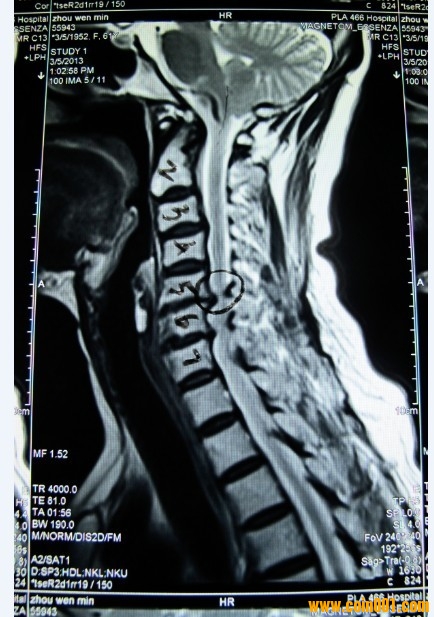

這是我丈母娘的頸椎核磁共振圖,5、6節(jié)頸椎椎管狹窄,問了幾家醫(yī)院都建議做手術(shù),

但是我丈母娘畢竟60多了,想盡量保守治療,有請網(wǎng)站懂這方面知識的會員給點建議,

建議是做手術(shù)好,還是不做手術(shù)好。哪個風(fēng)險較小。60多歲的人了,哪種治療方式更

適合她。謝謝了。

脊髓型頸椎?。?br />報告上應(yīng)該寫著的吧?頸髓受壓明顯,

一般得這個的都是建議手術(shù)治療,我估計你丈母娘應(yīng)該有些癥狀的吧?比如走路不穩(wěn)像踩棉花等等。嚴重者走路經(jīng)常摔跟頭,尤其天冷的時候,有時候腿甚至?xí)ブX無法行走。

這個如果是年輕人的話,手術(shù)越早越好,否則頸髓繼續(xù)受壓有可能會癱瘓。

手術(shù)一般采用的是椎管減壓,椎體間融合,鈦板內(nèi)固定融合術(shù)。費用一般在5,6萬元左右,如果有醫(yī)保,話花費也就2萬,北京治療這個一般建議去北醫(yī)三院或者協(xié)和都行。

一般如果手術(shù)的話,住院時間大概在7-10天左右,然后會定期復(fù)查。手術(shù)時間一般在4,5個小時左右,

手術(shù)后導(dǎo)尿管導(dǎo)尿,第2天拔掉,佩戴頸托后由主管大夫扶起,陪床的開始幾天會比較辛苦,要有思想準備。

現(xiàn)在的癥狀是一只手抬不起來,舉高就麻然后就抖。我丈母娘是會計,估計是長期低頭所導(dǎo)致,現(xiàn)在醫(yī)院給的建議是盡量不讓低頭。